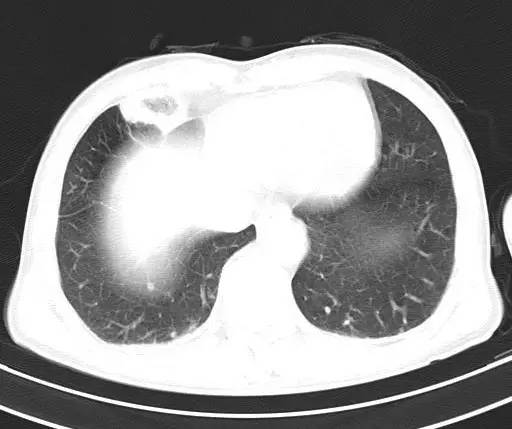

治疗前CT(图1-8):两肺胸膜下散在多发斑片状、结节状伴空洞影,边缘欠清晰。